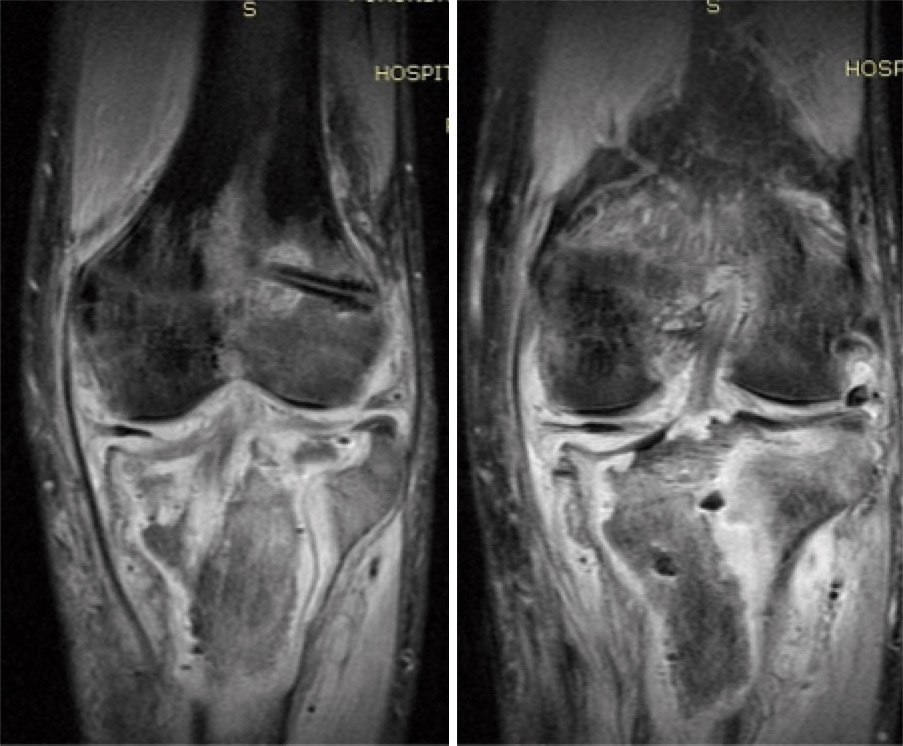

La evolución fue favorable, mejorando la clínica y los parámetros analíticos, resolviéndose la infección y consiguiendo una extensión de –5° y flexión de 95°, aunque persiste un defecto óseo epifisometafisario proximal en tibia izquierda, como se observa tanto en la radiografía como en la TC que se le realizaron tras un año de evolución, donde además se aprecia una artrosis femorotibial incipiente (Figuras 2 y 3).